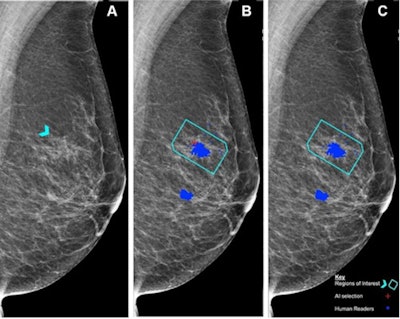

Chen and colleagues hypothesized that such performance metrics could be obtained for AI using similar methods. It sought to use test sets from the PERFORMS scheme to compare the performance of a commercially available AI algorithm (Lunit Insight MMG, version 1.1.7.1; Lunit) to that of radiologists reading the same test sets.

For the study, the investigators included 552 human readers who evaluated the test sets between 2018 and 2021; they used the AI algorithm to evaluate the test sets in 2022. The algorithm considered each breast separately, assigning a suspicion of malignancy score to features detected. The test sets consisted of 161 normal breasts, 70 malignant breasts, and nine benign breasts.